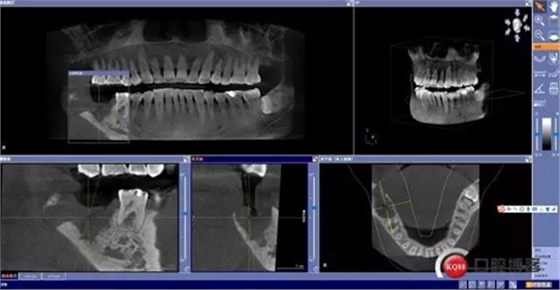

術(shù)前CBCT分析

X線及CBCT檢查:47、48根尖周區(qū)大面積低密度影像,波及下牙槽神經(jīng)管,部分區(qū)域至神經(jīng)管以下。CBCT顯示神經(jīng)管走形于47根尖炎癥區(qū)下方(已侵犯)48炎癥區(qū)頰側(cè)(已侵犯)

術(shù)后影像分析